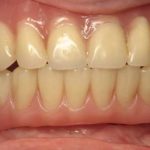

Peggy L.

This patient had broken her tooth and had an Implant placed to replace it.